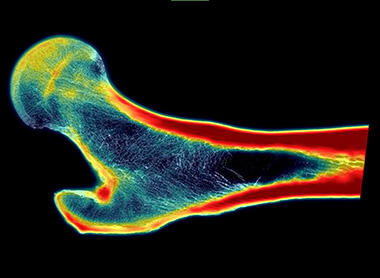

Artificial intelligence higher-resolution image of a femur microstructure from a CT scan

SwRI’s super-resolution technology, which uses artificial intelligence to create higher-resolution images from CT scans, produced this image of the femur microstructure. Clear images like this could help physicians better assess osteoporosis and fracture risk in patients.